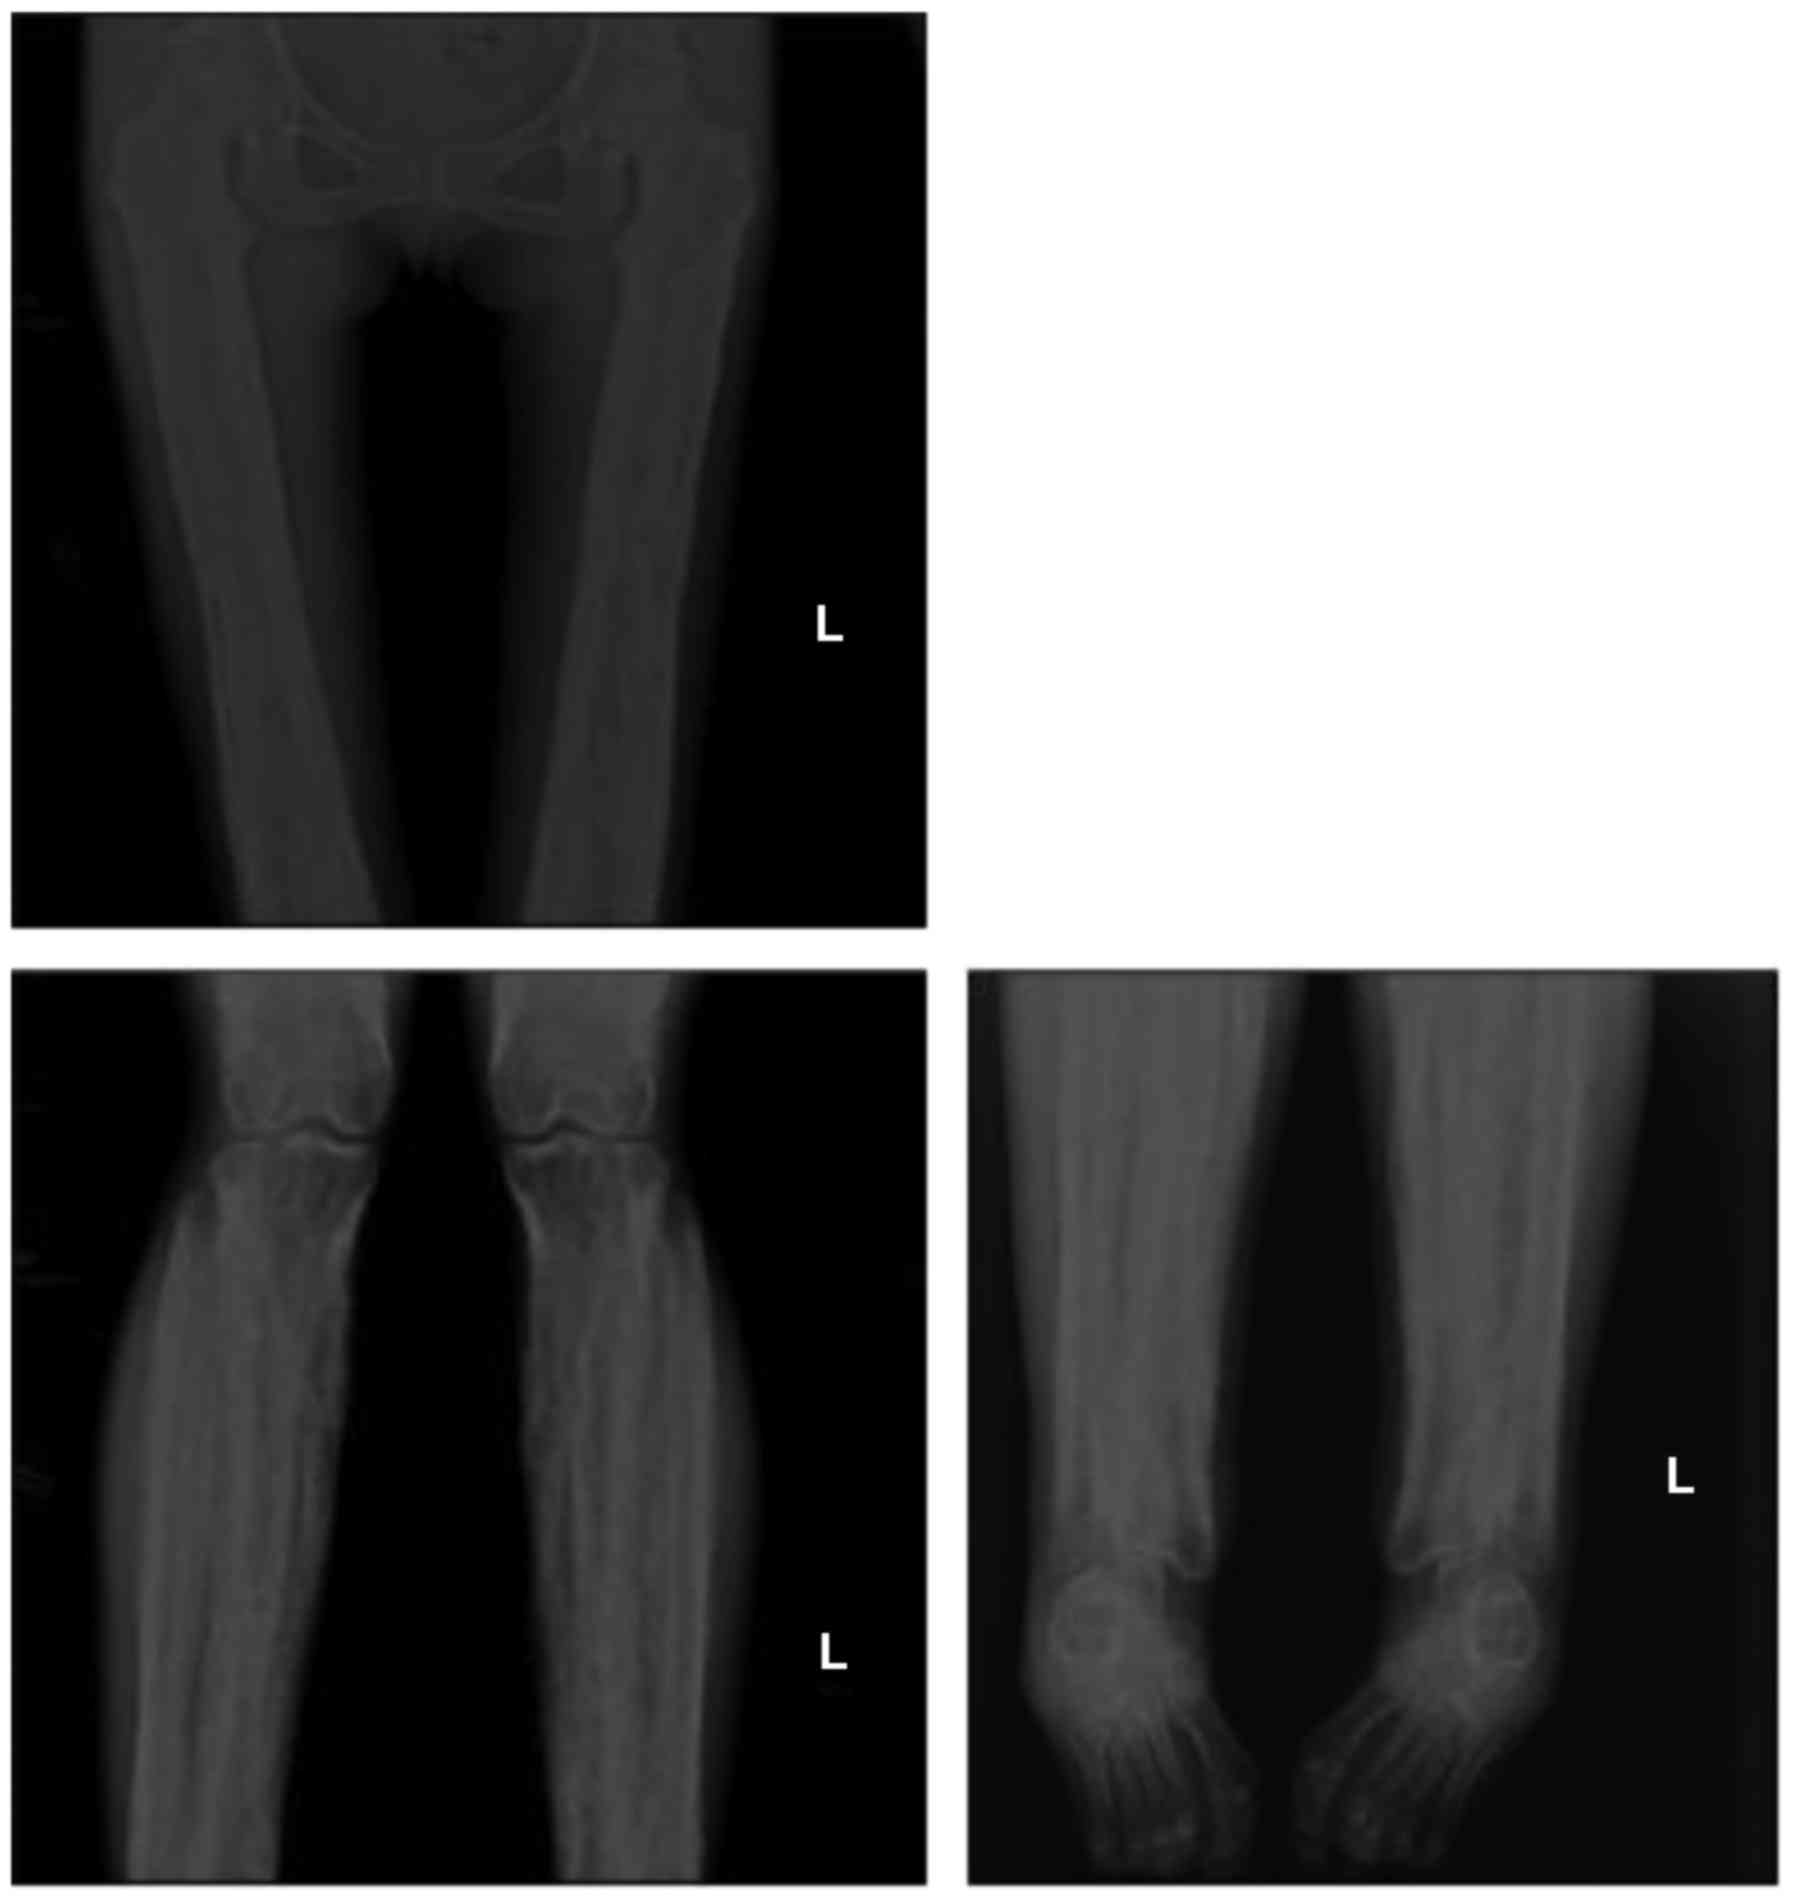

Radiographic images demonstrated cortical thickening of the diaphysis of long bones with irregular endosteal sclerosis. The bones involved included the humerus, radius, ulna, femur, tibia and fibula. The joint space between radius and ulna was narrowed in the patients, as well as the joint space of the tibia and fibula. The metaphysis and epiphysis of the long bones were unaffected (Figs. 2 and 3). Osteoproliferation and osteosclerosis of the ilium, acetabulum and ramus ossis ischii was observed (Fig. 4). The images also revealed periosteal thickening and sclerosis of the skull and facial bone. The diploe of skull disappeared, and the mastoid and sella turcica presented cortical sclerosis (Fig. 5).

Anteroposterior radiographs of the proband femur, tibia and fibula. Images revealed cortical thickening of the diaphysis with irregular endosteal sclerosis. The joint space of tibia and fibula was narrowed. Sparing of the metaphysis and epiphysis was noted. L, left.